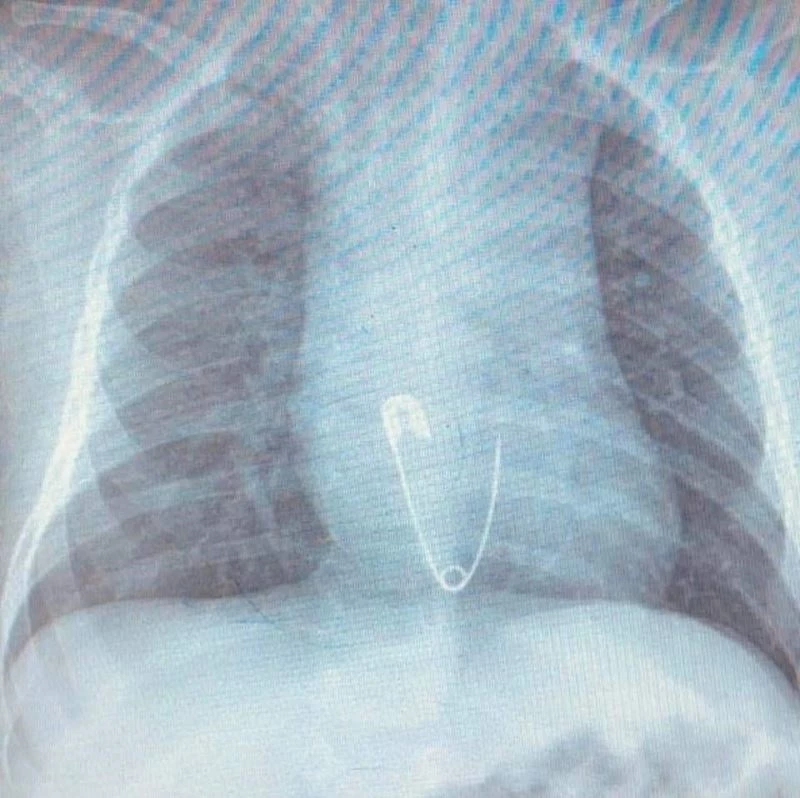

Yuttuğu çengelli iğne yemek borusuna saplanan 5 aylık bebek, Diyarbakır’dan Elazığ’a sevk edildi. Yapılan operasyonla iğne çıkarıldı.

Diyarbakır’da ikamet eden Esvet ile Amine Solmaz çiftinin tek çocukları olan 5 aylık Efraim’in nefes borusuna ailenin taktığı çengelli iğneli nazar boncuğu kaçtı. Aile bebeklerinin ağzına kaçan nazar boncuğunu çıkardı ama çengelli iğneyi çıkaramayınca en yakın hastaneye başvurdu. Burada yapılan ilk müdahalenin ardından bebek Elazığ’a sevk edildi. Ambulansla Fırat Üniversitesi (FÜ) Hastanesi Çocuk Gastroenteroloji Hepatoloji ve Beslenme Bölümü’ne getirilen bebeğin yapılan tetkiklerinde iğnenin yemek borusunun alt kısmında takılı kaldığı tespit edildi. Hemen Çocuk Endoskopi Ünitesine alınan bebeğin nefes borusundaki iğne, yapılan endoskopik yöntemle yaklaşık 15 dakikalık sürede çıkarıldı. Sağlık durumu iyi olan bebek ve ailesi taburcu edildi.

Hastanın Diyarbakır’dan Elazığ’a geldiğini belirten Prof. Dr. Yaşar Doğan, “Hastayı kabul ettik, 5 aylık bir hasta. Bize gelmeden önce üzerinde bulunan nazar boncuğunu çengelli iğne ile birlikte ağzına götürmüş. Aile de fark edince müdahale etmiş, ağzındaki nazar boncuğunu çıkarmış fakat o esnada çengelli iğne yemek borusuna kaçmış. Hasta geldiği zaman çektiğimiz röntgende çengelli iğne yemek borusunun alt kısmında takılı vaziyetteydi. Hastaya 15 dakikalık sedasyon altında işlem yapıldı, endoskopi ile parça çıkarıldı. Hasta şu anda gayet iyi. Biraz sonra da evlerine göndereceğiz” dedi.